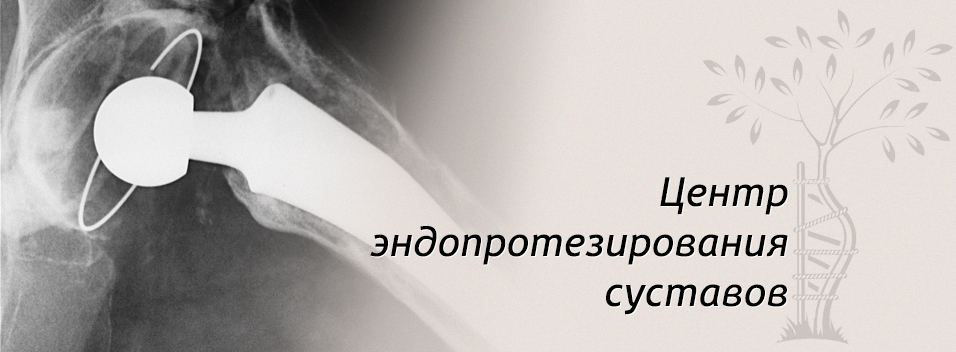

Предстоит замена сустава и протезирование